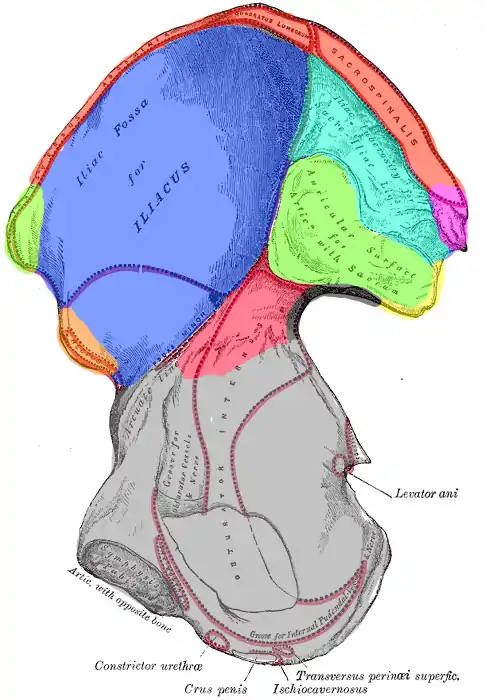

De to 'dele' af tarmbenet er opdelt af to strukturer: Linea arcuata og facies auricularis ossis illi. Facies og endda også tuberositas iliaca betragtes i noglet materiale[2] som del af corpus, hvilket vil sige at corpus overtager dorsalsiden af hoftekammen. I denne artikel betragtes linea arcuata og facies auricularis ossis illi som grænseområder og tuberositas iliaca som del af ala.

Facies auricularis ossis illi artikulerer med en tilsvarende knogleflade på korsbenet.

Corpus ossis illi

Corpus af tarmbenet er, set fra siden, formet som en affladet rektangel med en skrå hældning. Den nederste ende er med til at danne acetabulum og den øverste ende fascies auricularis ossis illi på indersiden. Øverst er corpus på indersiden afgrænset af linea arcuata, en forhøjning der løber imellem mødestedet af de tre hofteknogler og fascies auricularis ossis illi. Nederst er rektanglen indad konveks og indskæringen der dannes her kaldes incisura ischiadica major.

Corpus danner forbindelse med nabohofteknoglen os ischii, sædebenet. Den udgør også halvdelen af forbindelsen til skambenet sammen med ala ossis illi.

Ingen muskler insererer på corpus ossis illi, men et enkelt ligament, ligamentum sacroiliacum posterius, har strøj der hæfter bl.a. til dorsal-enden af corpus.

Ala ossis illi

Vingen af tarmbenet udgør langt størstedelen af knoglens overflade og indeholder talrige overfladeegenskaber, bl.a. for at kunne fungere ordentligt som sæde for de talrige muskler der insererer på denne.

Den frie overkant af ala betegnes crista iliaca, eller hoftekammen på dansk. Langs hoftekammen findes en række knoglefremspring. Forrest langs grænsen til skambenet er spina iliaca anterior inferior og lige superiort for denne er spina iliaca anterior superior. Bagtil findes den bagud-pegende spina iliaca posterior superior og under denne, ved dorsalenden af incisura ischiadica major, findes spina iliaca posterior inferior. Hoftekammen ender ved posterior inferior og ala overgår her til corpus. Lidt dorsalt for spina iliaca anterior superior, pegende lateralt ud fra kroppen på ydersiden af ala, findes desuden også tuberculum iliacum.

Den antero-mediale flade af ala er lateralt-konveks og kaldes fossa iliaca og den tilsvarende musculus iliacus har origo fra denne.